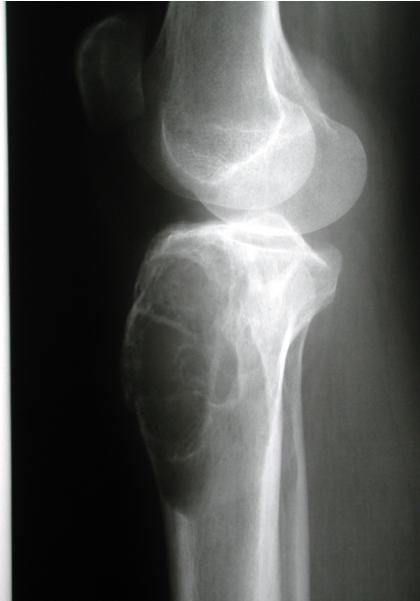

site: distal femur size: Most (involving how much? / cm?) matrix: mixed - mainly radiopaque , wide zone of transition, cortical destruction, resulted periosteal reaction, and codman’s triangle soft tissue involvement: